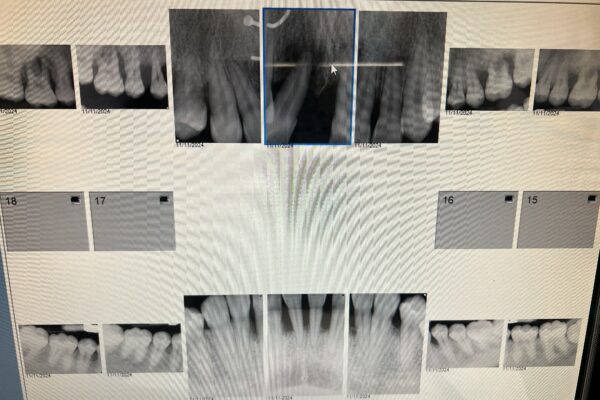

• Tough tough overall case. Patient is a 15yo female with aggressive perio. Cases like this take careful planning and consideration because youre trying to plan for the next 60+ years.

I’m partnering with a prosthodontist for this case and we have a tentative tx plan but I’d love to hear outside opinions!